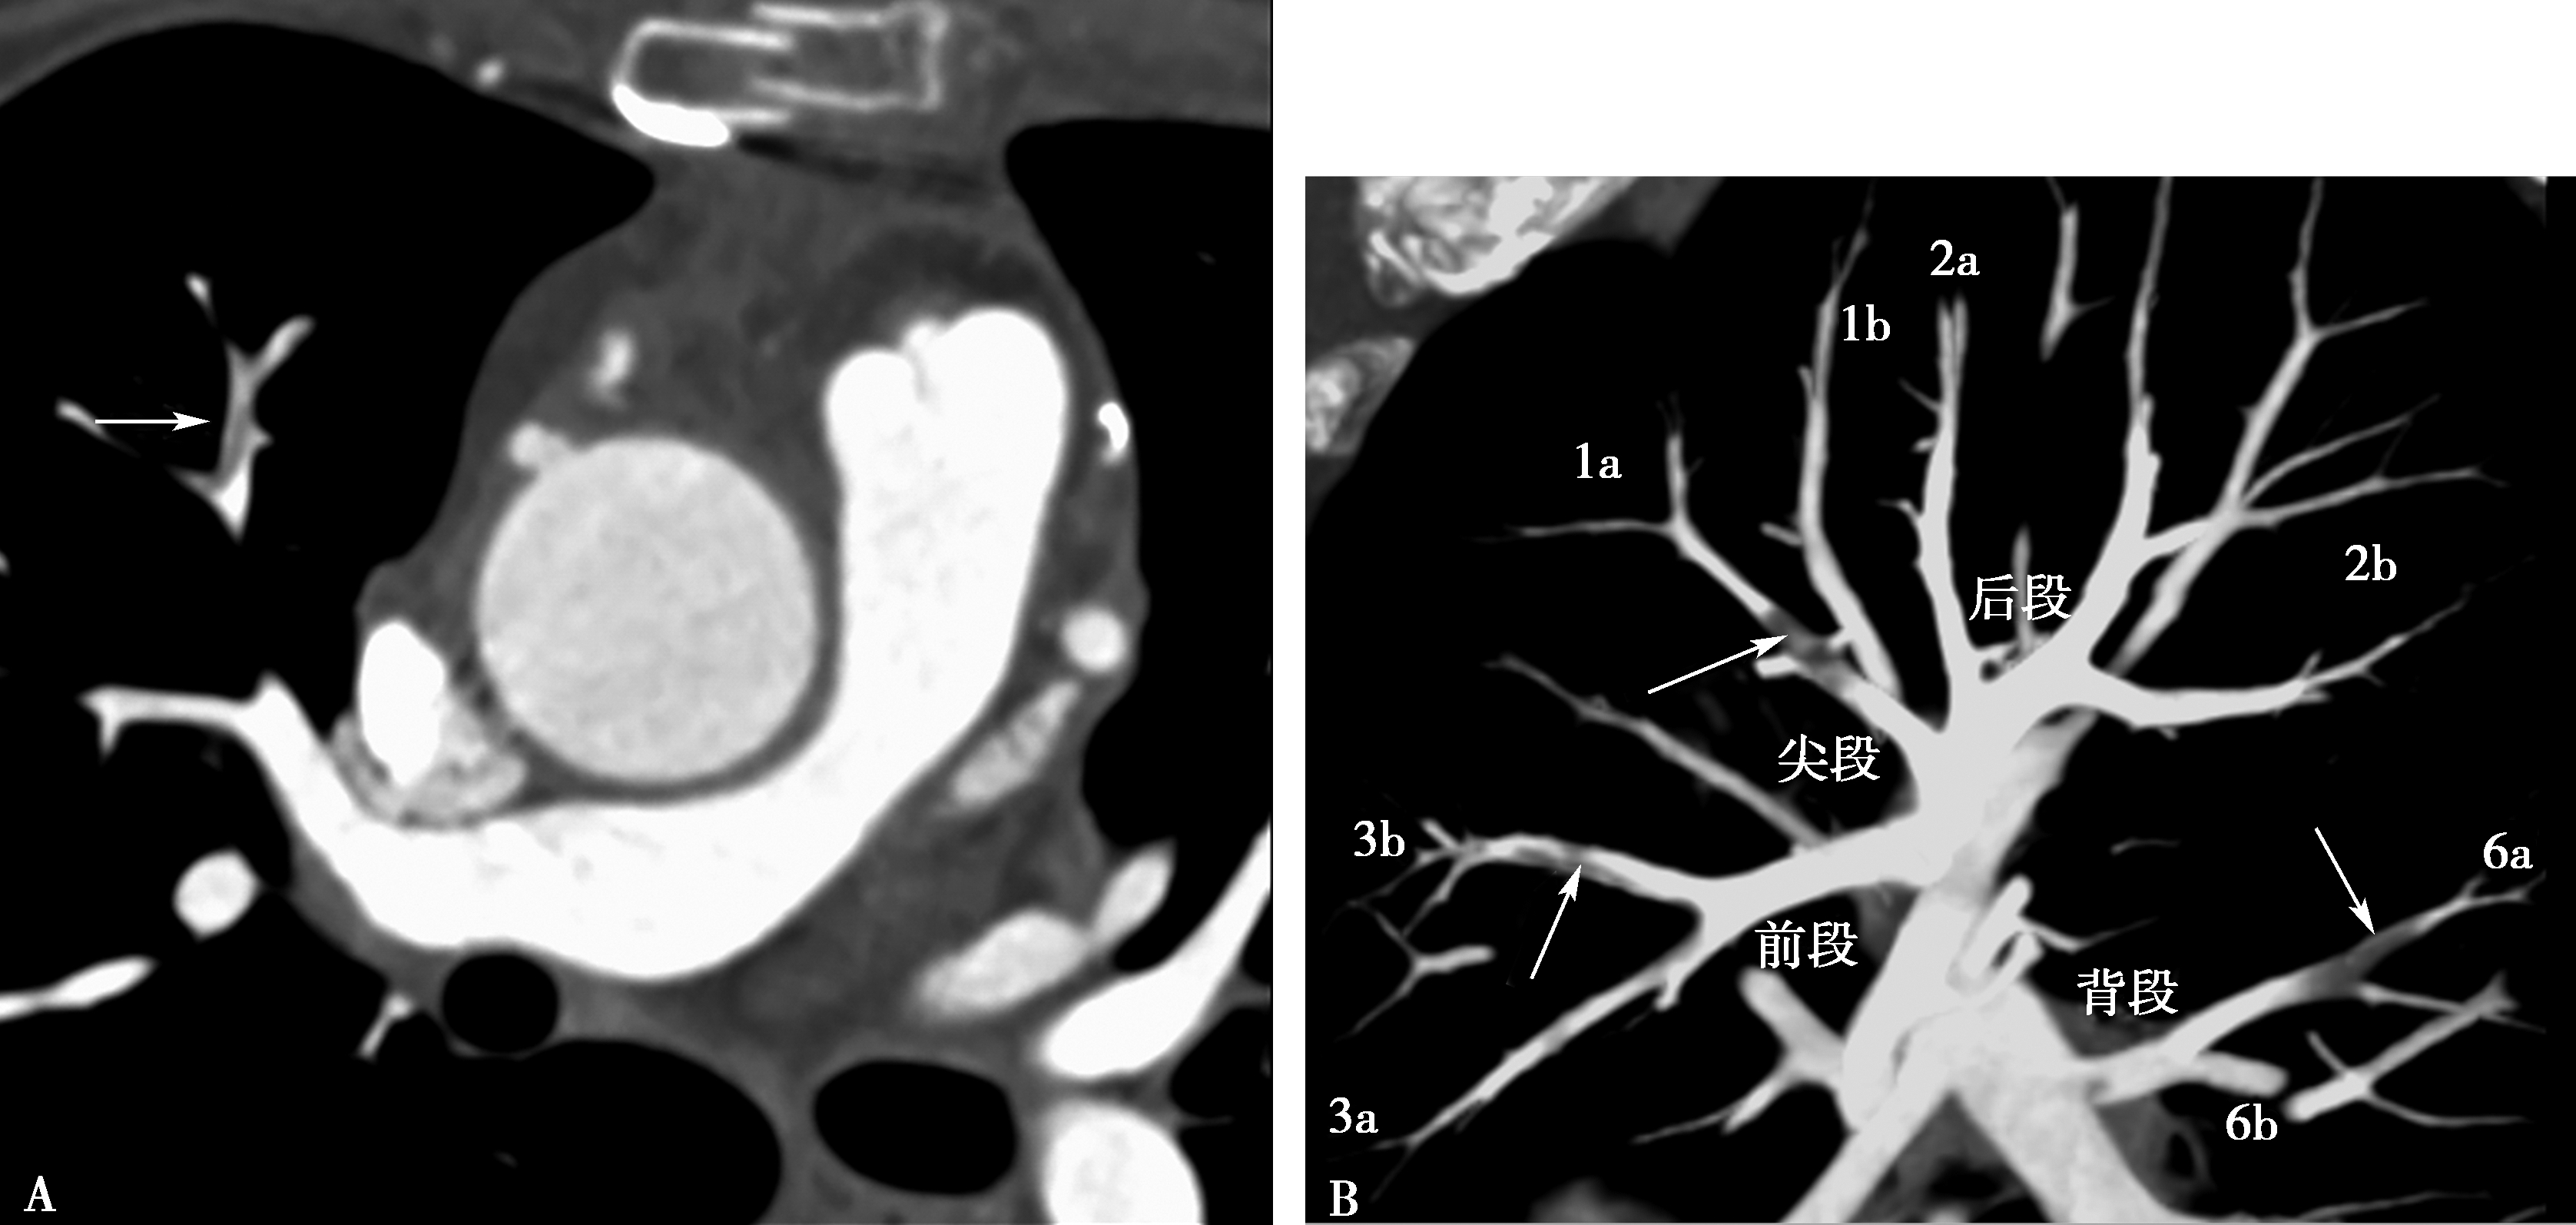

图8-5-5 男,28岁,反复口腔及生殖器溃疡5年,白塞病,肺动脉瘤

A.胸部X线片,示左右肺动脉瘤(↑);B.横断图像,左、右下肺动脉动脉瘤形成,附壁血栓形成(↑);C.多层重组(冠状位)示右下肺动脉动脉瘤合并附壁血栓(↑);D.多层重组(左前斜位)示左下肺动脉瘤合并附壁血栓形成(↑)。CT诊断:左右肺动脉瘤,附壁血栓形成,病变性质白塞病